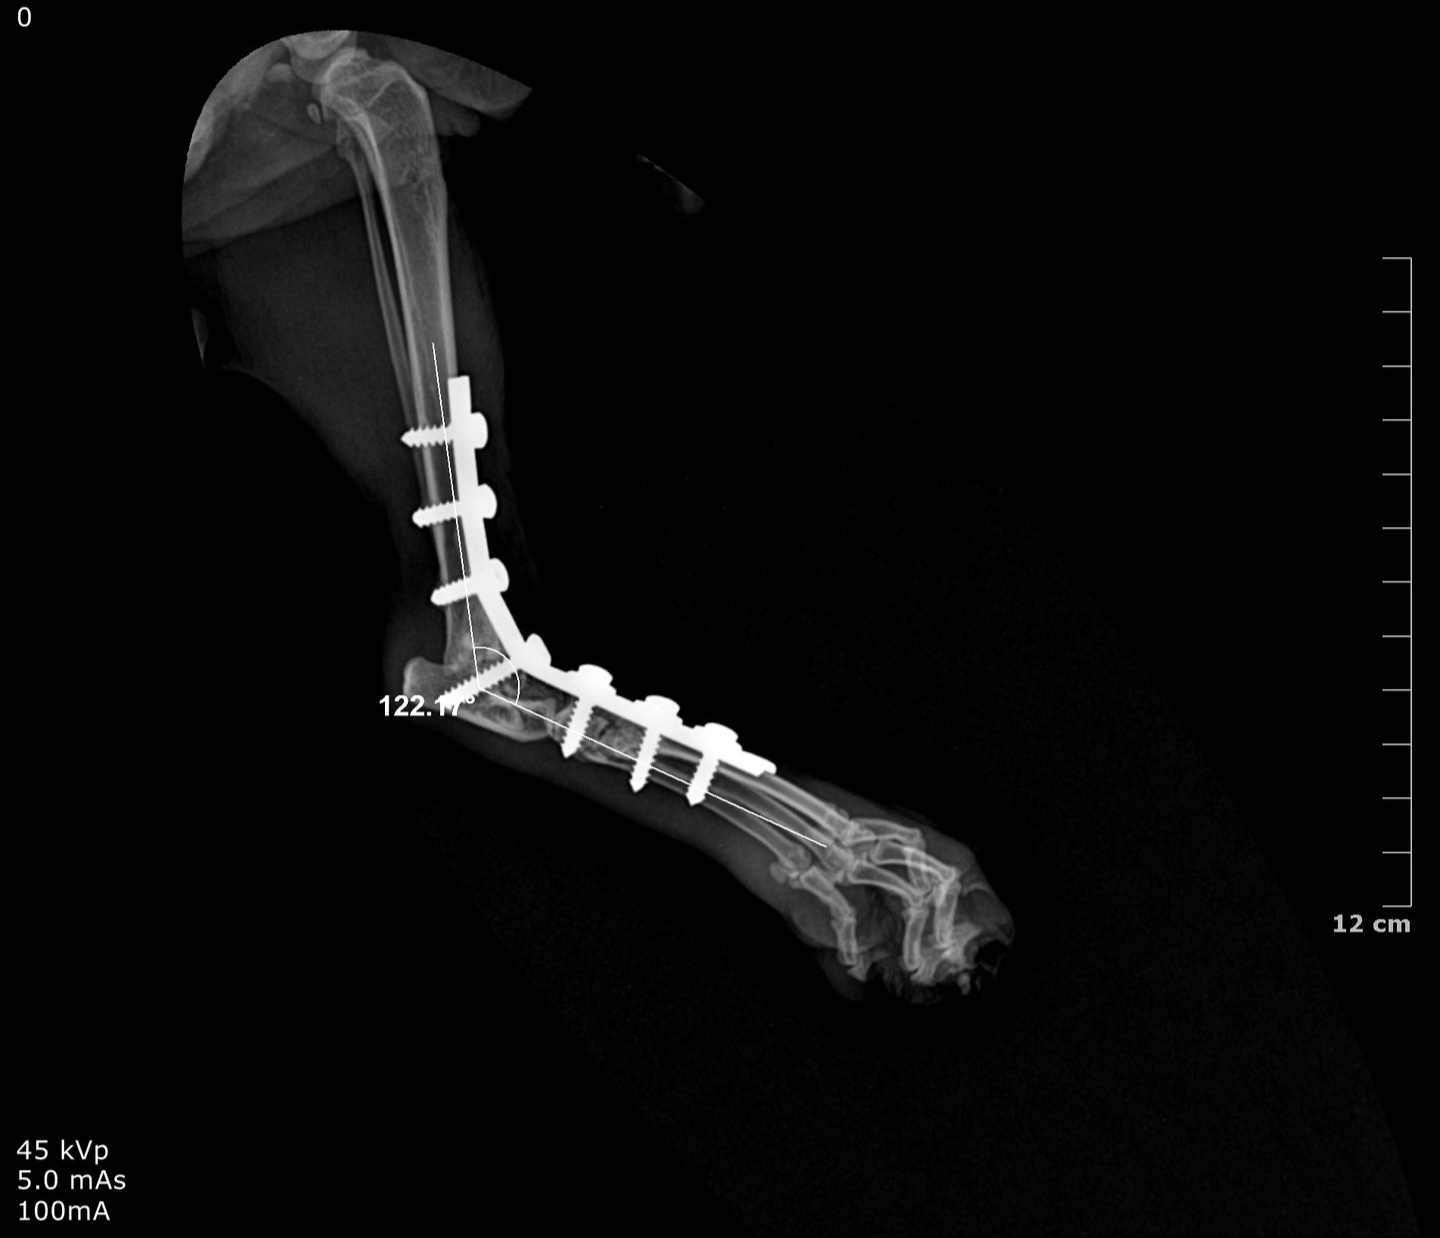

Pan-tarsal Arthrodesis

Pantarsal arthrodesis is a surgical procedure that involves the fusion of all joints within the tarsus (hock) including the tibiotarsal, intertarsal, and tarsometatarsal joints into a single solid bone unit

It is performed to restore a stable, pain-free limb when the tarsal joint complex is irreparably damaged or unstable

Surgical Treatment: Pantarsal Arthrodesis